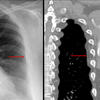

Aortic nipple

Ex 1 CT

Date: 03/23/2004

Views: 5587